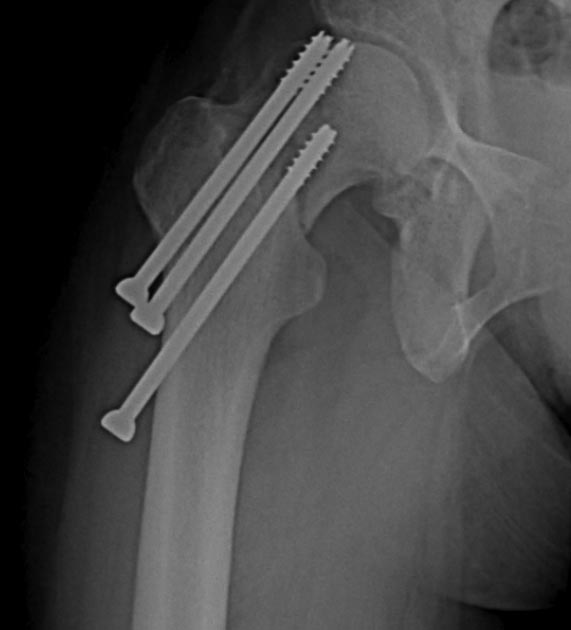

Две несросшихся шейки бедра, пацинтка 27 лет, травме 5 месяцев

БИОС плеча, Чкдо на л/запястный сустав, Биос левого бедра, Мос правой шейки бедра винтами.

Причина обращения -выявленный ложный сустав шейки левого бедра. При дообследовании выявлен несросшийся перелом шейки бедра на винтах.

Опороспособность обеих н/конечностей резко снижена, может стоять на правой, передвигается на каляске.Что думаем: слева однозначно протез, но бедро не срослось, менять гвоздь на пластину, пластина или которкая, или опасность конфликта с ножкой протеза, можно подождать консолидации и разбираться с правой конечностью.Справа остесинтез с коррегирующей остеотомией, но смущает состояние верхнего полюса после миграции винтов, что может повлечь протезирование на фоне нарушения анатомии проксимального бедра, что не хорошо для выживаемости протеза у 27 летней пациентки. Может сразу протез ?КТ головки не информативна из-за винтов